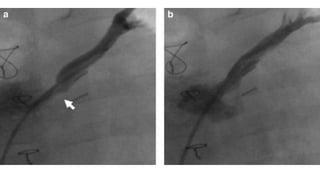

PULMONARY VEIN STENOSIS •Incidence - 5- 15% • Usually occurs within the first 6 months • Pathophysiology ✦ Diffuse fibrotic thickening of PV ✦ Localised narrowing at PV-LA junction ✦ May or may not be associate with anastomotic stenosis • Presentation ✦ Progressive Dyspnea • Investigation ✦ Echocardiography ★ PV Flow velocity > 2m/s ✦ Cross Sectional Imaging

• 104.

• 108.

CTA • Narrowing inPV just proximal to insertion into common chamber/LA

• 109.

PULMONARY VEIN STENOSIS •Treatment ✦ Steroids or Chemotherapy to minimise fibrosis ✦ Balloon dilatation/stenting ✦ Ostial endarterectomy of intimal hyperplasia IRevising the common pulmonary vein to left atrium anastomosis with or without patch enlargement ✦ Sutureless repair

• 115.

• Developed PVO- 71/406 (17.5%) ✦ Cardiac - 9/67 (13%) ✦ Supracardiac -25/205 (12%) ✦ Infracardiac - 25/110 (23%) ✦ Mixed - 11/37 (30%) • Median time to diagnosis from surgery - 49days ( 0 - 5.9 yrs) ✦ Diagnosed within 6 months of surgery - 59/71 (83%) ✦ Echo - 30% , Angiography - 54% and CT/MRI - 16% • Intervention ✦ 60 patients required intervention ✦ 56 received intervention ★ 50% required more than 1 intervention